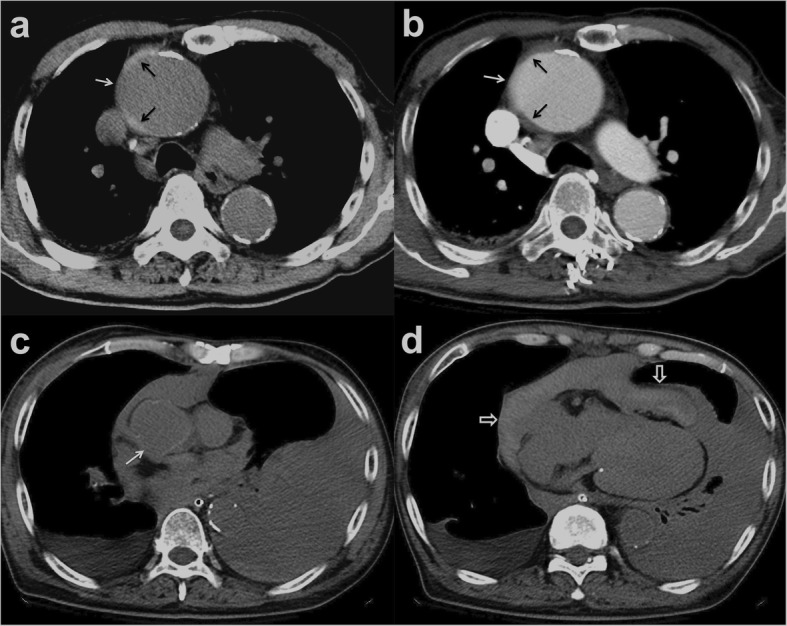

Patients 1 to 5 had initial medical treatment and stable status for 1 to 3 days suffered sudden death. Patient 1 with type A IMH (Fig. 2a, b) had sudden cardiovascular collapse 2 days later, and follow-up CT revealed aortic rupture and hemopericardium (Fig. 2c, d). Patient 2 with type B IMH had recurrent symptoms after 2 days, and follow-up CT showed adventitial tear with partial outward spillage of hematoma (Fig. 3). Patients 6 to 9 had early surgical or endovascular management recovered uneventfully. Patients 6 and 7 demonstrated ascending aorta ecchymosis with adventitial tear and intact intima at surgery (Fig. 4), and patient 8 had IMH with impending ascending aortic rupture. Pathologic examinations confirmed aortic IMH.

Fig. 2.

a Unenhanced axial CT shows a smooth central defect (white arrow) in the hyper-attenuating crescentic hematoma (black arrows) along the ascending thoracic aorta. b Enhanced CT shows a focal out-bulging (white arrow) of the aortic lumen, with smooth obtuse edges corresponding to the defect on unenhanced study and non-enhancing crescentic hematoma (black arrows). Note the absence of intimal flap or contrast medium extravasation. c, d Unenhanced follow-up CT shows rupture of the ascending aorta (white arrow), hemopericardium (open arrows), and left pleural effusion

Imaging features in patients with broken-crescent sign

A definitive CT diagnosis of aortic IMH was established based on the presence of hyper-attenuating crescentic aortic wall thickening on unenhanced CT. In a retrospective review, all nine patients exhibited a distinctive, positive broken-crescent sign in CT, with a smooth focal defect in IMH that corresponded to a smooth out-bulging of the aortic lumen with obtuse edges on the subsequent enhanced study (Figs. 2, 3, and 4). All nine patients demonstrated smooth aortic lumen with neither intima flap nor contrast medium extravasation, indicating an intact inner wall of the aorta. There were no substantial differences in maximum aortic diameter (range 42–52 mm, mean 47.0 mm vs. range 43–53 mm, mean 47.5 mm) or maximum IMH thickness (range 5–8 mm, mean 5.6 mm vs. range 4–7 mm, mean 5.3 mm) between the deceased (5/9) and surviving (4/9) patients, respectively. Of note, among eight out of 104 patients with in-hospital mortality, broken-crescent sign was retrospectively identified in five patients. Of these eight patients, three demonstrated minimal hemopericardium in CT but no other specific imaging sign for prediction of dismal outcome could be sought. Furthermore, there were no significant differences in maximum aorta diameter and maximum IMH thickness between in-hospital mortality and survival groups (49.4 ± 7.1 mm vs 46.8 ± 11.8 mm, p = 0.571; and 8.8 ± 4.2 mm vs 9.1 ± 5.8 mm, p = 0.373, respectively) (Mann-Whitney test).